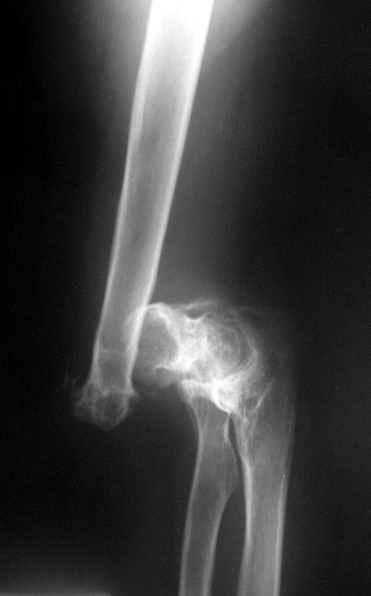

The recent x rays show established Non union with poor quality bone in the distal fragement. The joint is also appearing degenerate. In view of the multiple failed reconstructive surgeries, an Elbow replacement would seem reasonable.

Obviously there is no elbow joint...the options are few: (from the worst to the "best"...if any)